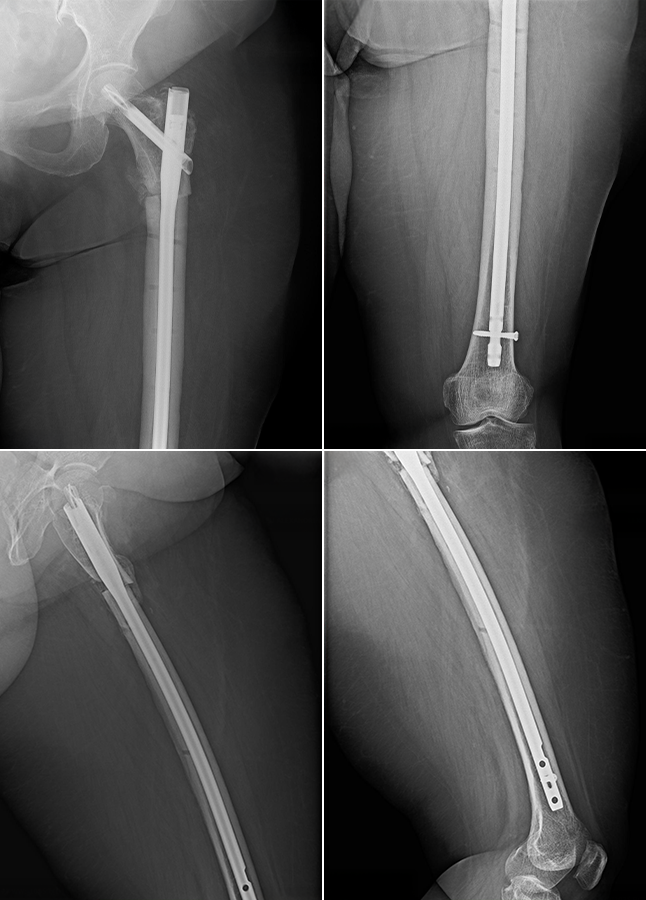

Controalele imagistice efectuate la 6 săptămâni, 3 luni și 6 luni au evidențiat o evoluție locală favorabilă, cu reluarea treptată a sprijinului și îmbunătățirea funcției membrului inferior stâng.

Imaginea 2. Examinare imagistică la 3 luni după tratamentul chirurgical al pseudartrozei de femur proximal